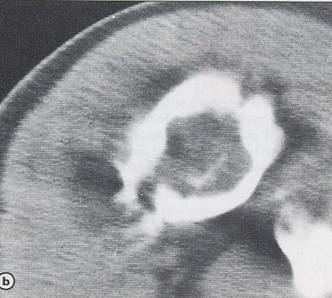

Chondrosarcom

b)humerus dr

proximal, distructie corticala, extensie in parti moi